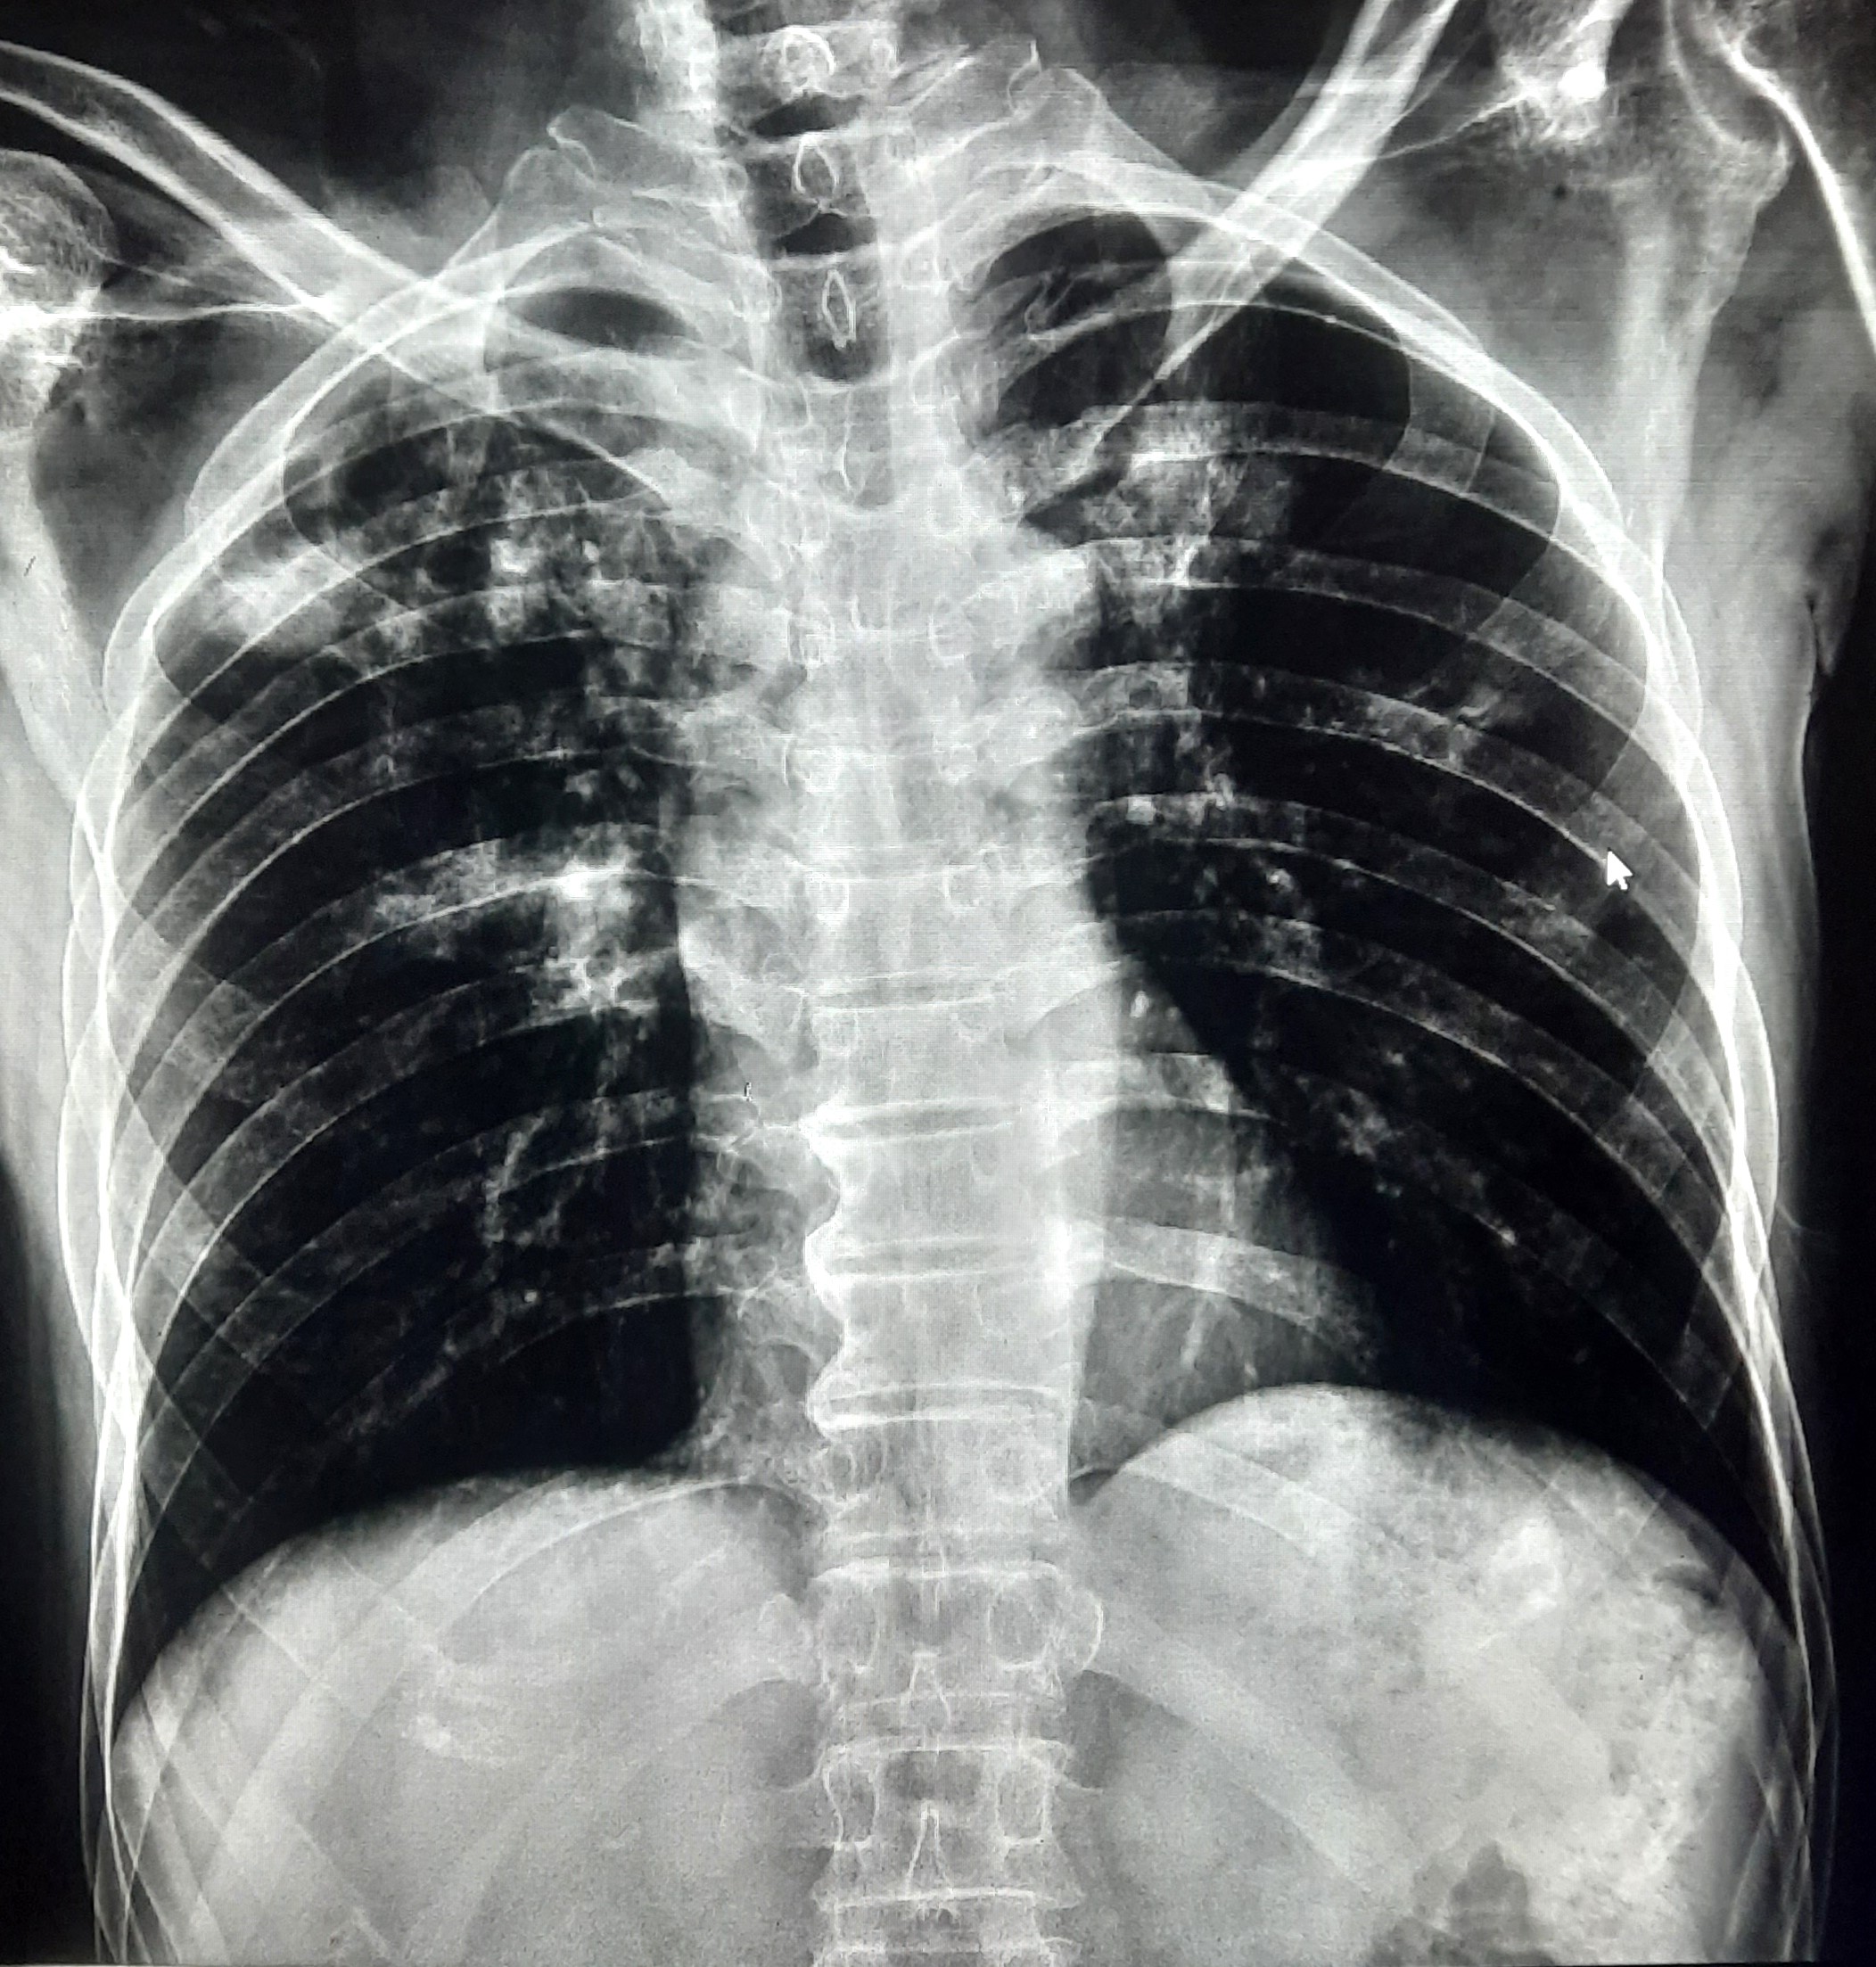

| 102 | IGGMC, Nagpur, Nagpur | P2 | 29-4370 | Prachi Bawane | Consent taken on Paper | 17 Yrs. |

Provisional Diag : PTB?

Final Diag : Active Pulmonary Tuberculosis With Tuberculi? Right Sided Pleural Effusion |

TB Case (Confirmed) | Bilateral ill Defined, No Homogenous Reticulonodular opacities, Right CP Angle Blunting | Abnormality visible on x-ray |